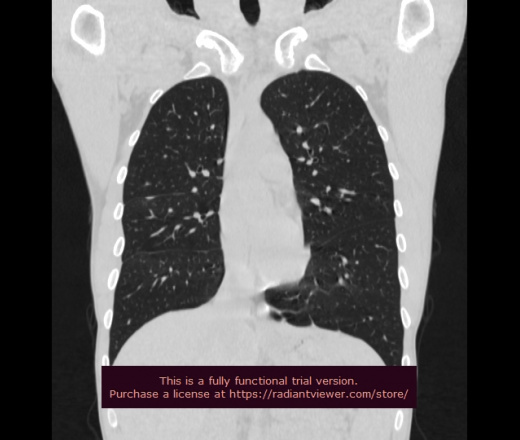

Молодой М20 лет, в июле травма грудной клетки, переломы 7-8 ребер справа и правой лопатки. В последствии на КТ междолевое скопление жидкости и жидкостные образования паренхимы с КП+20+25Ед.Н., а также дренированная полость. Температуры нет, кровь спокойная, из жалоб боли и тяжесть в грудной клетке справа.

Похоже на посттравматические ретенционные кисты. Одна опорожнилась

- скорее травматическое пневматоцеле, которое заполнилось

Вообщем дополняю анамнез, т.к. сам не знал много. Травма была тяжелая, оказывается было проведено КТ, где имелось обширное повреждение легочной паренхимы, гемопневмоторакс. Получается это гематомы паренхимы с лизированной кровью, включая междолевую, все так и было, просто теперь рассасывается, одна гематома опорожнилась.

- посмотреть бы те КТ-изображения;

- "опорожнилась" -  и заполнилась воздухом?